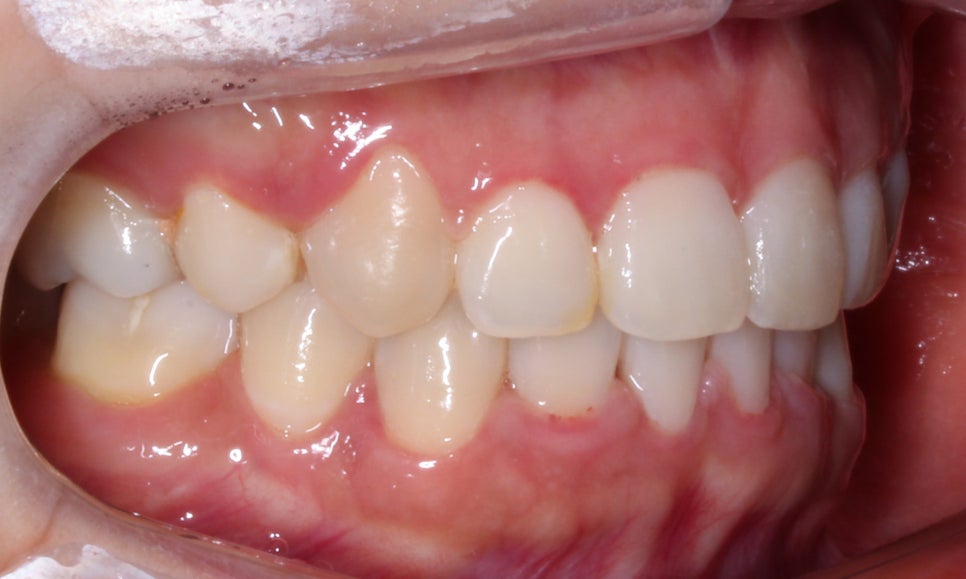

송곳니덧니 case의 좌우 교합평면 사진입니다.

측면에서 치아의 높이를 보면 보다

명확하게 high canine 증상을 확인할 수 있는데요,

송곳니는 우리의 치아 가운데 가장 길이가 긴

치근을 가지고 있기 때문에 성공적인 교정

결과를 기대하시는 경우 이 송곳니의 위치를

올바른 위치로 이동시키는 것이 중요합니다.

또한 사진에서 작은어금니와 잇몸 사이의

경계 부분에 나타나는 치아의 파임 증상은

치경부마모증이 일부 진행된 것으로 보이는데요,

위처럼 법랑질만 미세하게 손상된 초기일 경우

레진이나 Gi 치료만으로 수복이 가능하나

상아질까지 손상된 경우에는 크라운 등

넓은 범위의 보철치료가 필요할 수 있습니다.